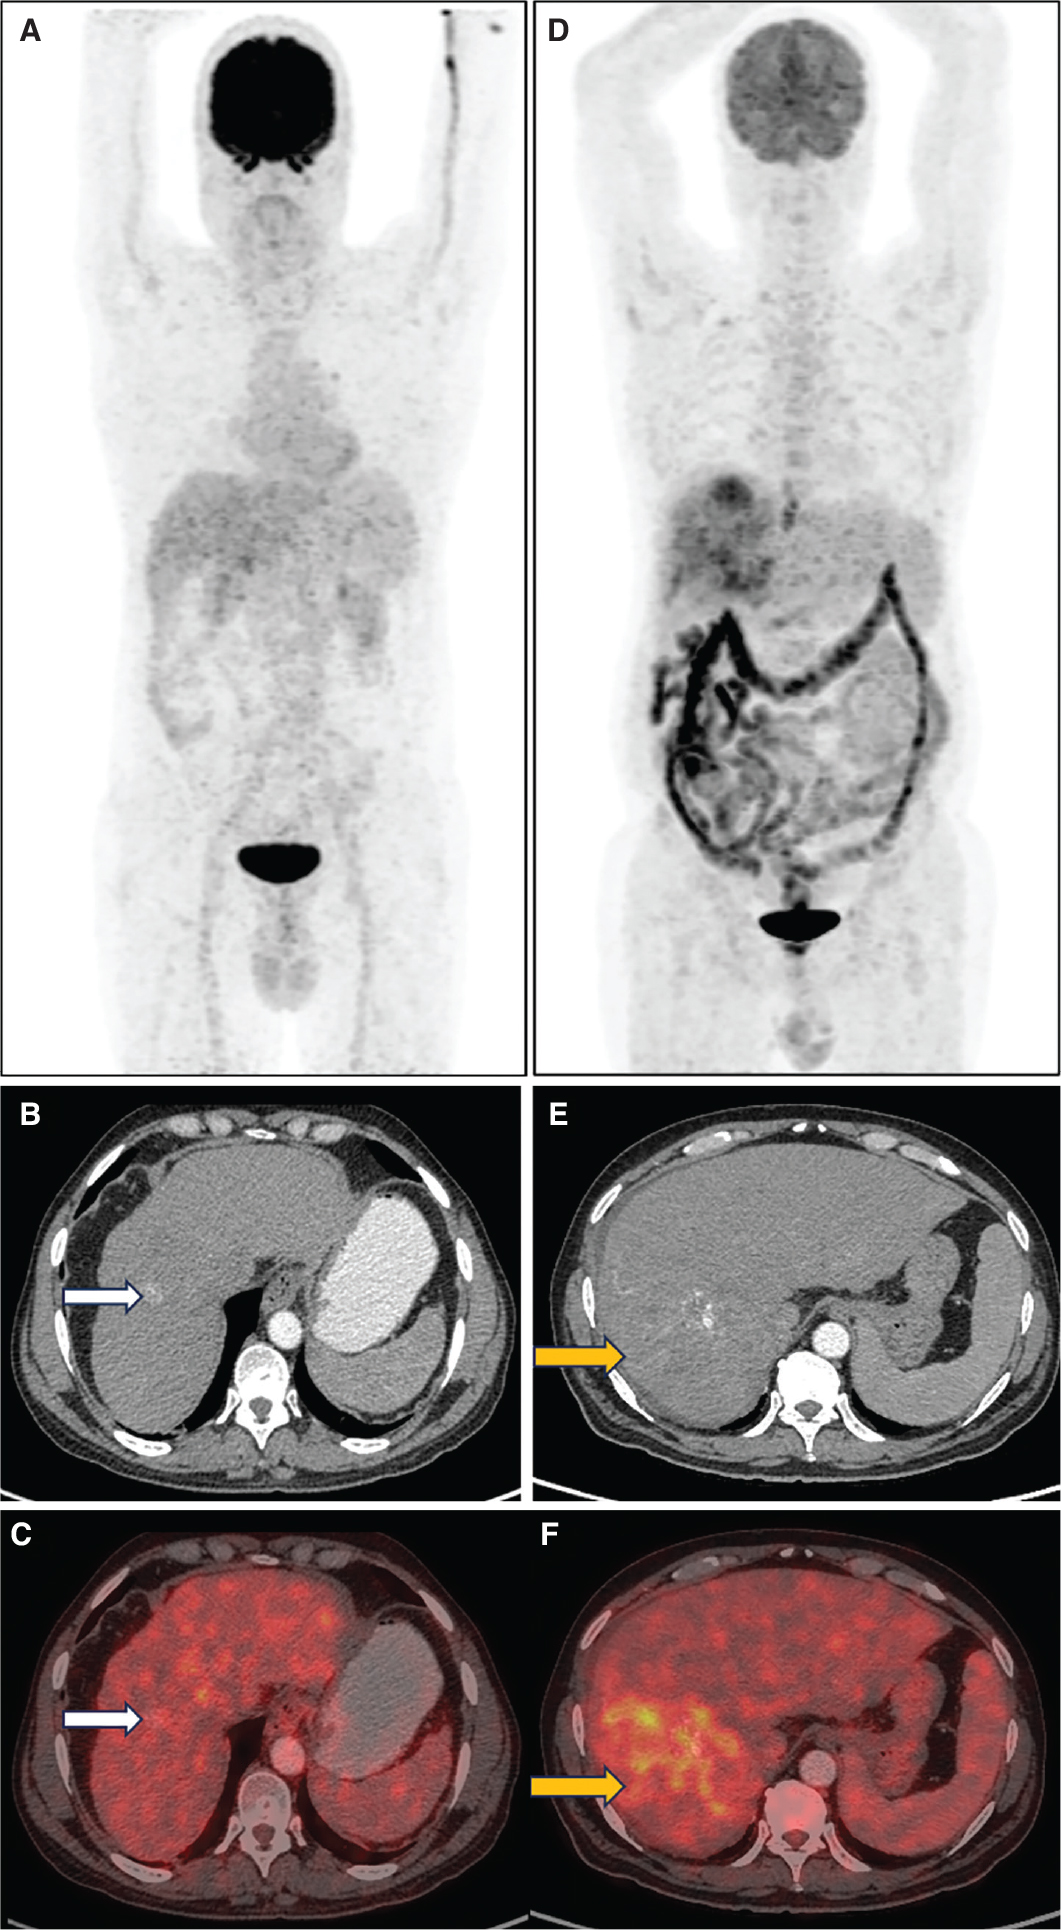

Fibroblasts associated with malignancy are known to be involved in tumor growth, migration, and progression. Fibroblast activation protein (FAP) is a serine protease highly expressed in cancer associated fibroblasts (CAF). As CAFs make about 90% of the gross tumor mass, targeting FAP inhibitor (FAPI) for imaging can aid in the visualisation of the tumor stroma. Guo et al. compared CECT, liver MRI, 68Ga-FAPI and 18F-FDG PET/CT in diagnosing primary and metastatic lesions in patients with HCC. Thirty-four individuals with hepatic lesions were included in the study and underwent concomitant 68Ga-FAPI-04, 18F-FDG PET, and CT scans. In the detection of primary liver tumors, the sensitivities of CECT, MRI, 68Ga-FAPI-04, and 18F-FDG PET/CT were found to be 96%, 100%, 96%, and 65%, respectively (19). 68Ga-FAPI PET/CT also has the potential to open the door for theranostic treatment option with therapeutic radionuclides in select patients showing 68Ga-FAPI uptake. Figure 2 (A-D) shows comparison of 18F-FDG and 68Ga-FAPI PET in a case of HCC.

Fig 1

Figure 2. 18F-FDG, 68Ga-FAPI PET/CT in HCC and 68Ga-DOTANOC PET/CT in NET. A. Maximum Intensity Projection (MIP) image of 18F-FDG PET/CT showing increased tracer uptake in the left lobe of liver in a case of HCC. Corresponding fused 18F-FDG PET/CT (B) image shows a non-FDG avid lesion in segment VII of liver (white arrow) and FDG avid lesion in left lobe. C. MIP image of 68Ga-FAPI PET/CT in the same patient showing areas of increased FAPI uptake in both lobes of the liver with corresponding fused transaxial 68Ga-FAPI PET/CT (D) image showing FAPI avidity (SUVmax 9.8) in the same segment VII and left lobe liver lesions (green arrow). 68Ga-FAPI PET can detect more lesions with higher tracer uptake compared to 18F-FDG PET-CT in HCC. E. MIP image of 68Ga-DOTANOC PET/CT in another patient with neuroendocrine tumor showing intense tracer uptake in the liver in multiple areas. Corresponding fused axial PET/CT image (F) shows intensely somatostatin receptor expressing lesions in both lobes of the liver, consistent with metastatic NET. 68Ga- DOTANOC PET/CT is highly specific for neural crest origin tumors.

Molecular imaging methods useful in diagnosis, staging and metastasis evaluation of NETs include 111In-pentetreotide somatostatin receptor scintigraphy (111In-SRS), 68Ga-DOTATATE, 68Ga-DOTANOC, and 18F-DOPA PET/CT for well-differentiated tumors and 18F-FDG PET/CT for high grade tumors. Somatostatin receptor (SSTR) overexpression is present in 60–90% of these tumors and is an essential mechanism for SRS. Of these, somatostatin receptor subtype 2 is expressed by 85% of NETs. Recent experience with 68Ga-labeled somatostatin analogue PET imaging shows higher sensitivity as compared to 111In-SRS and 99mTc-SRS. 111In-SRS and 99mTc-SRS are used less due to lower sensitivity and resolution compared to 68Ga-DOTA-NOC/TATE PET/CT. The diagnostic efficacy of 68Ga-DOTATATE PET/CT was compared to that of 99mTc-octreotide SPECT/CT and CT/MRI by Fallahi et al. In this prospective study, 25 NET patients who had been referred for an octreotide scan for suspected or proven NET were included. On a patient-based analysis, the sensitivity for CT/MRI, 68Ga-DOTATATE PET/CT, and 99mTc-octreotide SPECT/CT, respectively, was 71%, 90%, and 65%. The specificity of 99mTc-octreotide SPECT/CT, 68Ga-DOTATATE PET/CT, and CT/MRI was 80%, 80%, and 75%, respectively (21). Figure 2 (E-F) shows 68Ga-DOTANOC PET/CT images in a case of metastatic well-differentiated NET.